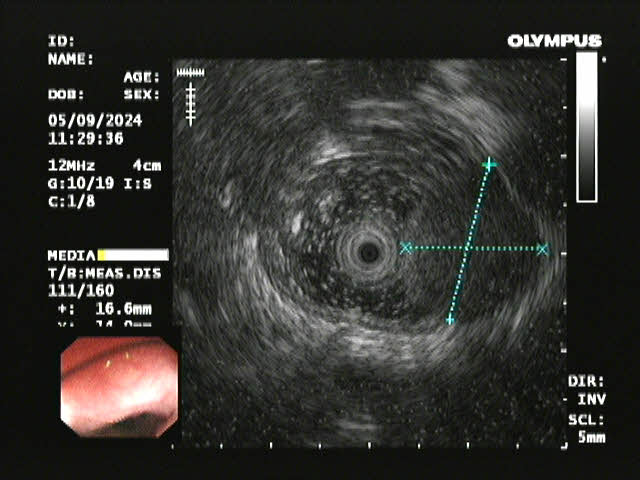

超声内镜

患者李某因胸骨后异物感20余天入院,在外院进行胃镜检查提示食管距门齿约26cm处见黏膜下肿瘤,在亚洲色吧 附二院超声胃镜提示该肿瘤呈低回声,局限于黏膜下层,固有肌层完整;胸部CT提示该肿瘤直径>2cm,位于食管中下段,增强扫描轻度强化,前与左主支气管相邻,后紧贴胸主动脉,手术过程中稍有不慎就可能发生大出血,危及患者生命,手术难度和风险可想而知。